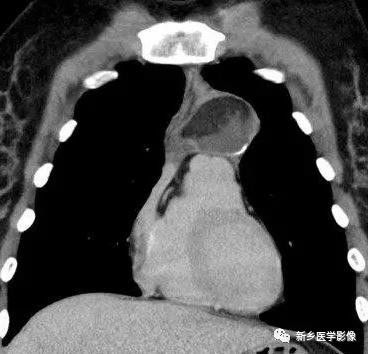

3.MRI表现:平扫示肿块与肌肉信号相似,增强后轻度强化。肿块内可有囊变,T1WI呈低信号,T2WI呈高信号。侵袭性胸腺瘤包膜不完整,环绕肿块的纵隔脂肪被侵蚀。